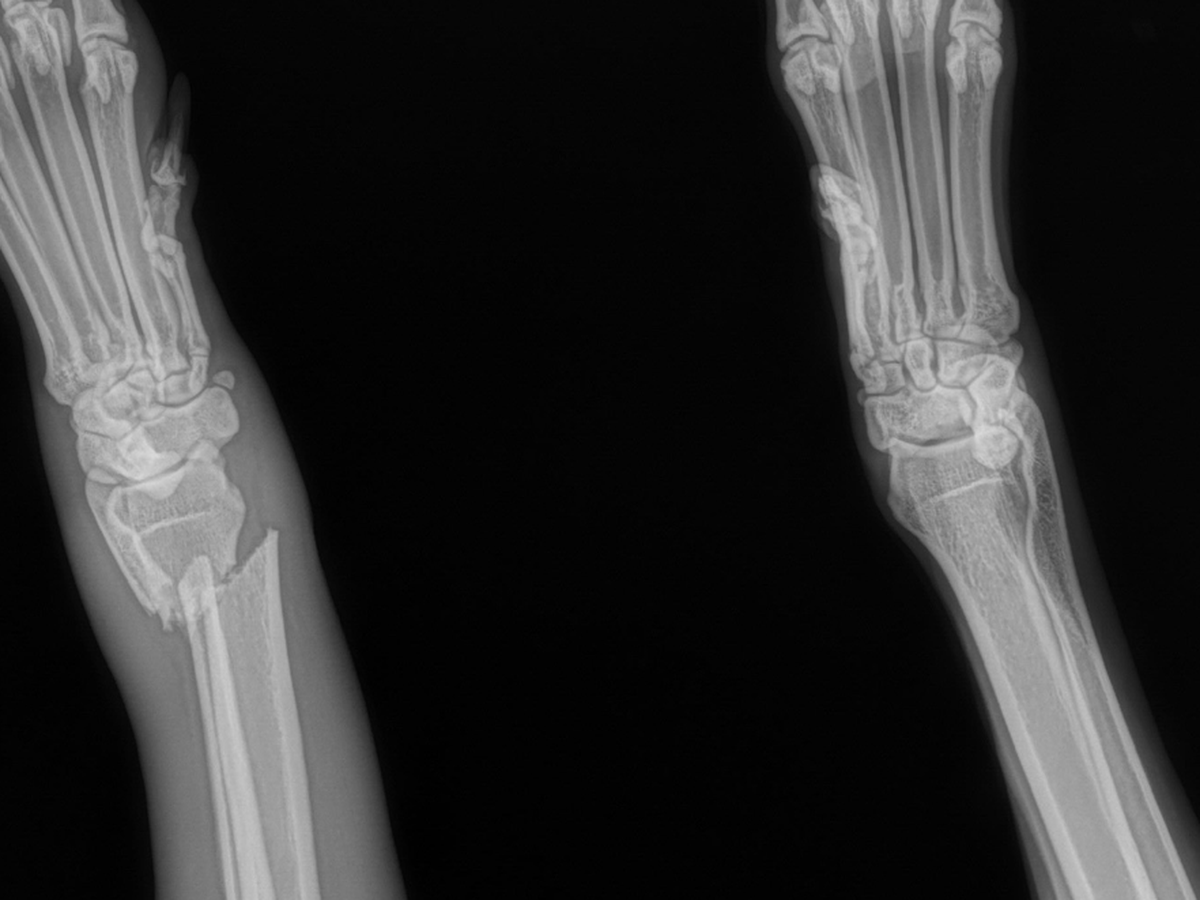

My dog Lu got loose and went on an adventure yesterday. She’s usually pretty crazy and gets herself hurt. I’d never imagine she’d hurt herself this bad. I took her to the vet today to see what they can do. She’s getting a splint and some pain meds to help with the pain, but unfortunately, that’s not going to be enough. Her carpus is broken in a weird spot and will require surgery. If it heals how it is with the splint, the doc said it would cause problems down the line with arthritis and consistent problems and pain. She’ll need surgery within a week; otherwise, it’s going to start to heal, and she’d need to get it rebroken. The good news is it’s a clean break and didn’t puncture the skin. Any help would be greatly appreciated.